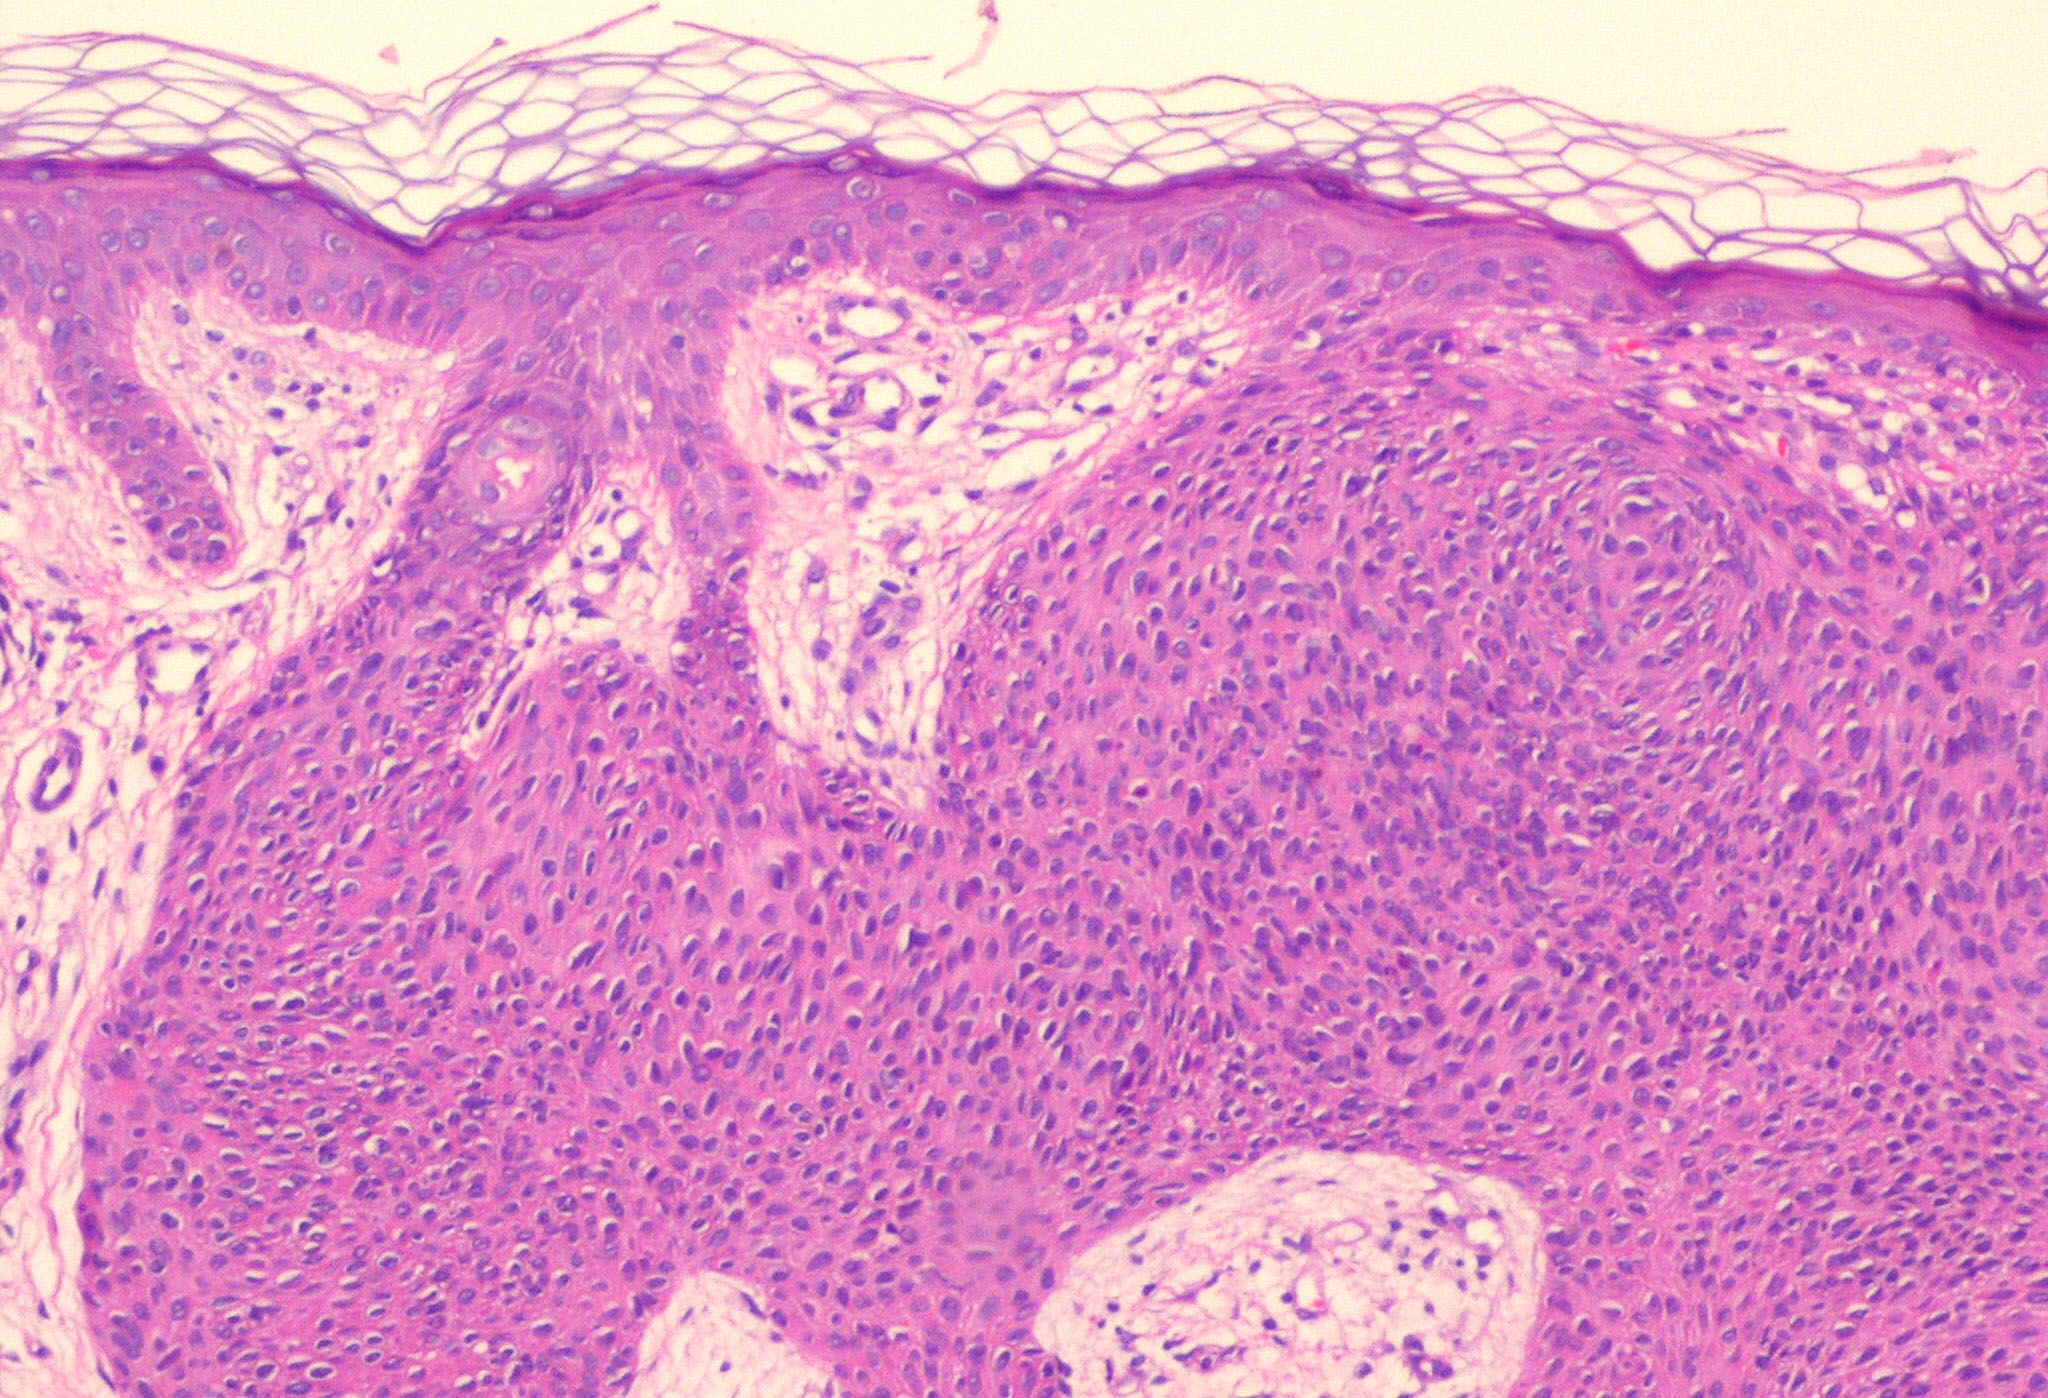

Hidroacanthoma_simplex = الشوكوم العرقي البسيط

OLYMPUS DIGITAL CAMERA